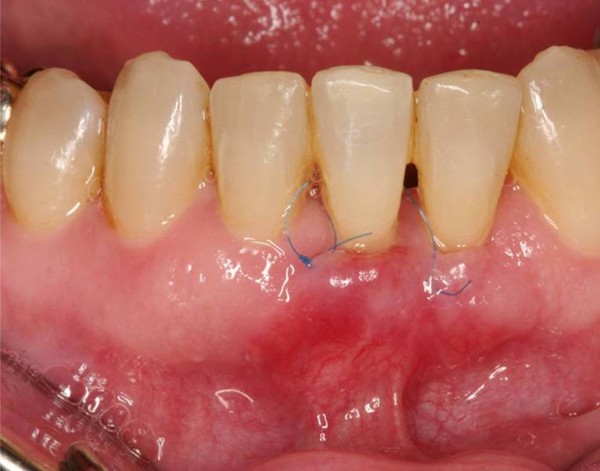

Figure 7From: Interdisciplinary approach for the treatment of periodontally compromised malpositioned anterior teeth: a case reportClinical situation 10 days postoperative.Back to article page